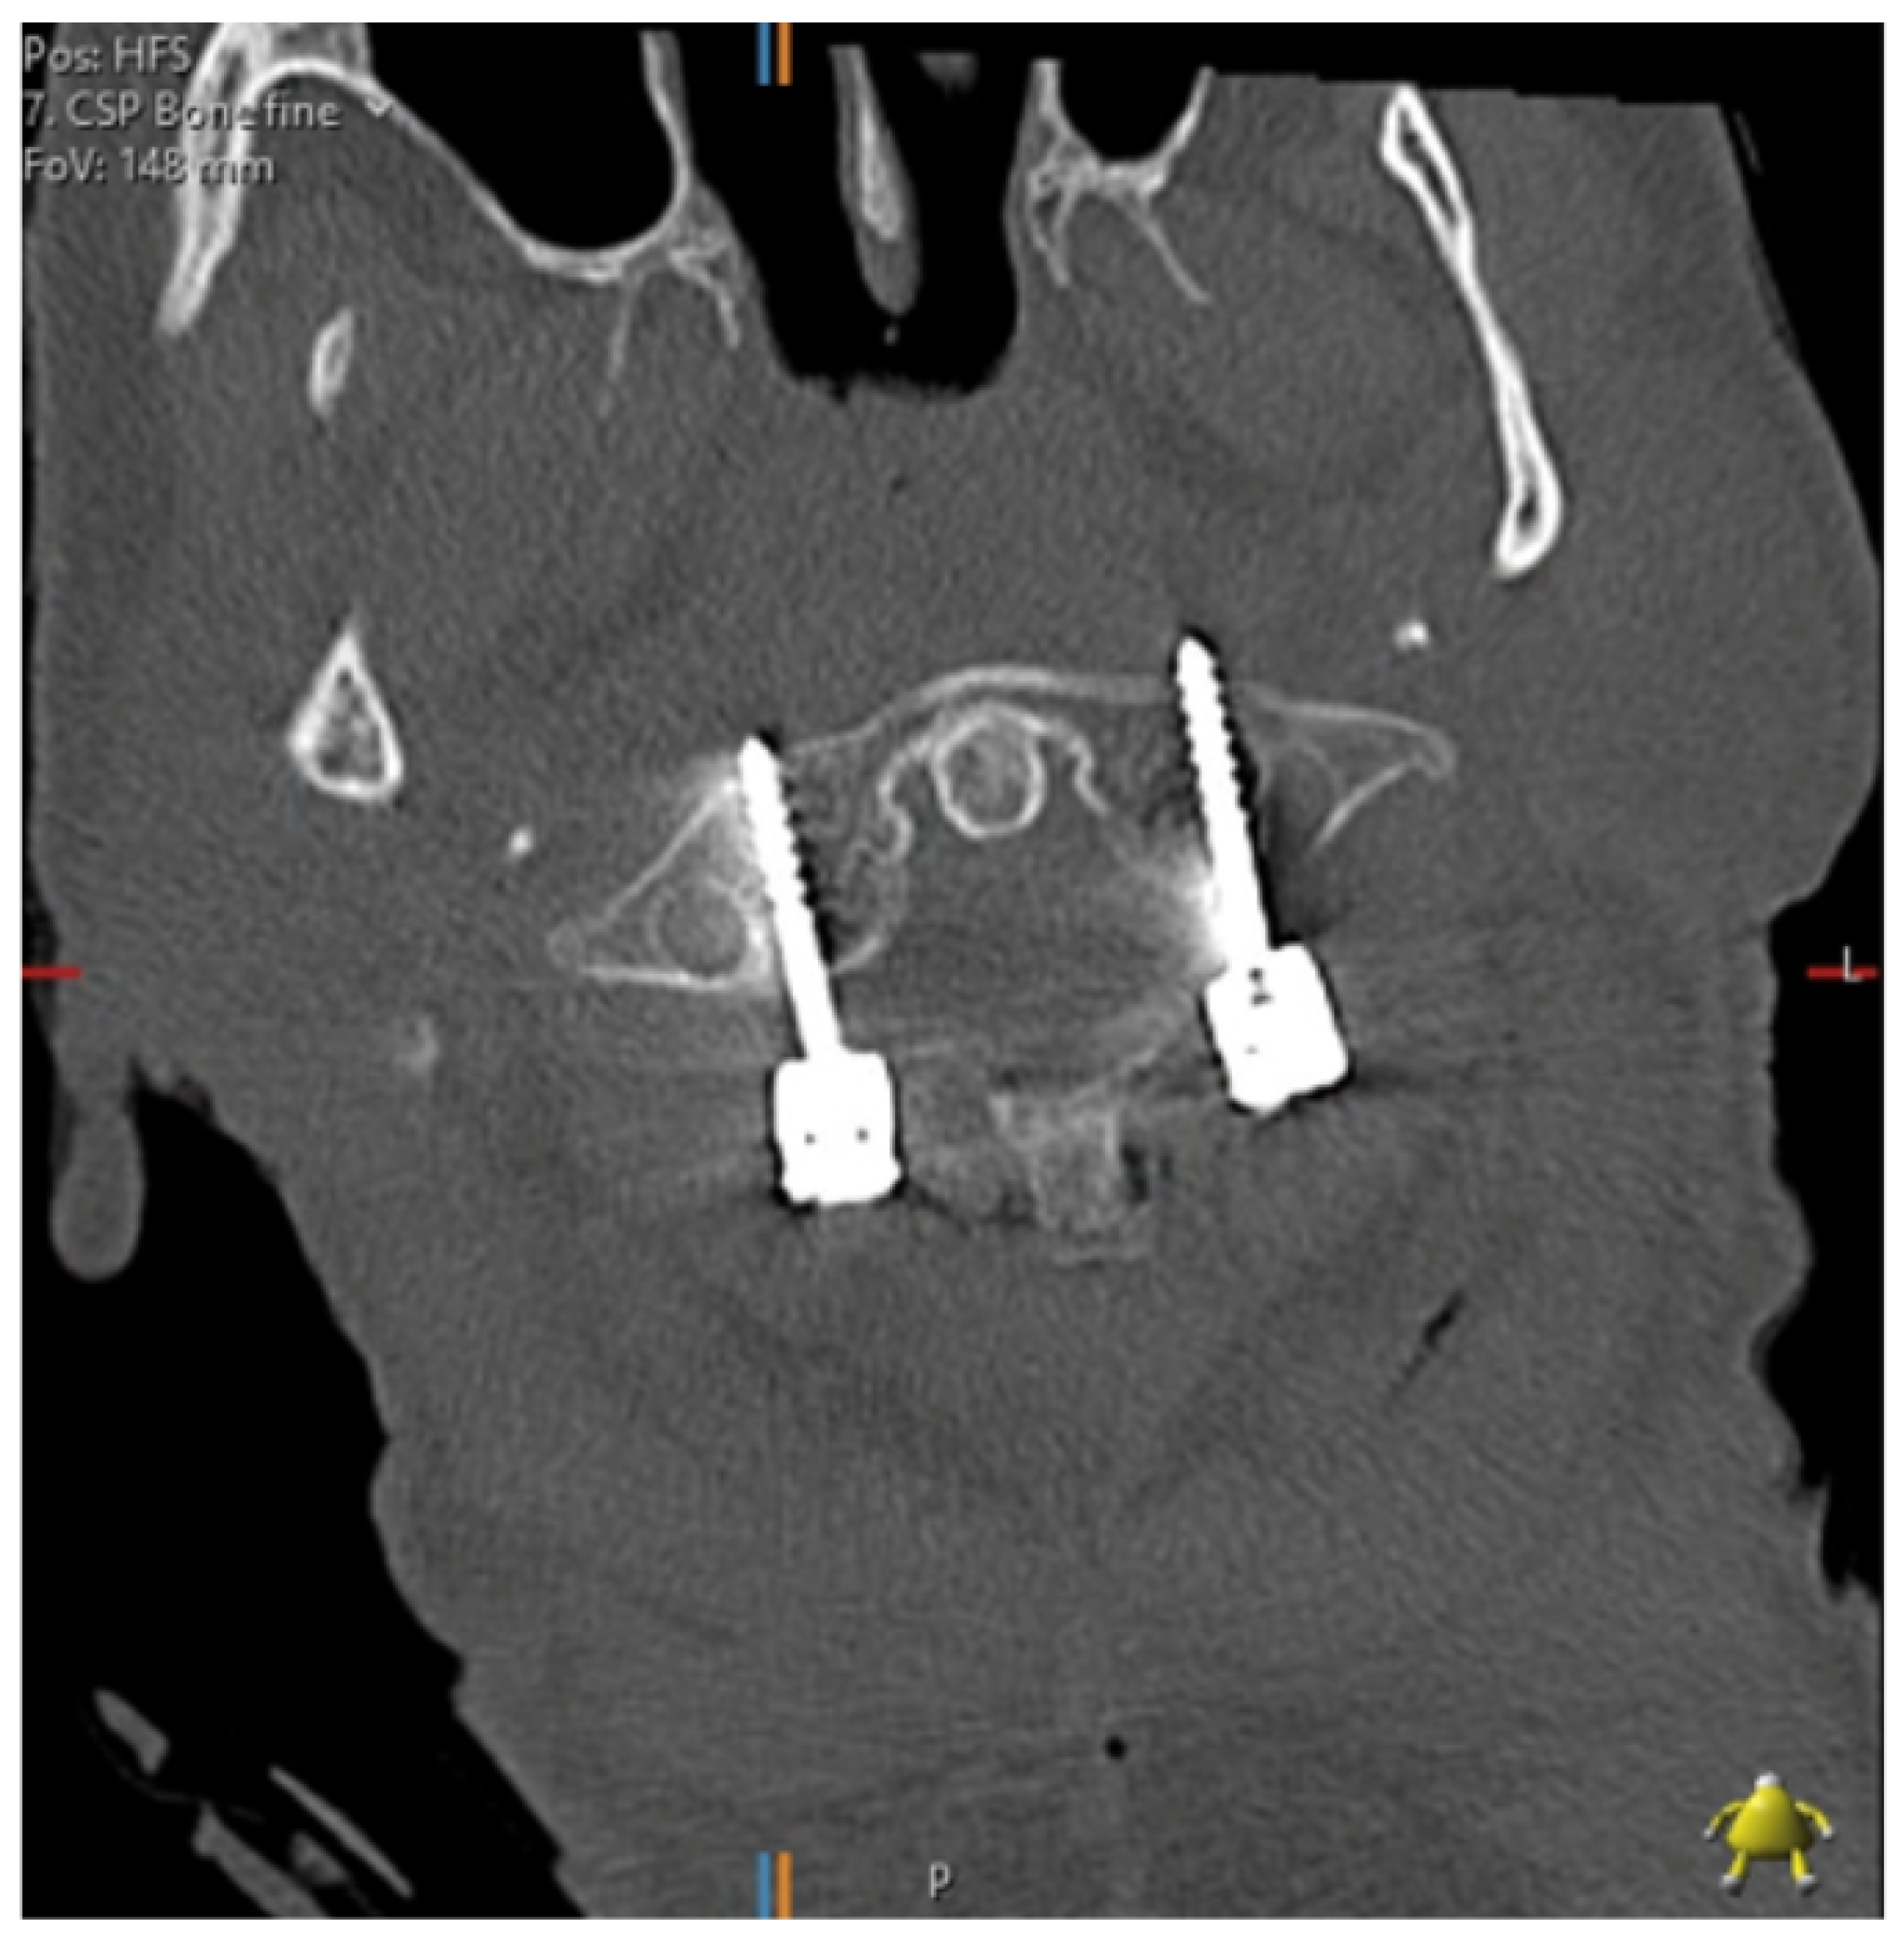

Pedicle screw insertion in the cervical spine is complicated by the smaller pedicle widths, the larger transverse pedicle angles and the proximity of the vertebral arteries, nerve roots and spinal cord. Factors affecting anatomy include gender, age, height and race [6]. Figure 1 shows a post-operative axial CT image of a patient who underwent cervical spine pedicle screw fixation with a fatal injury to the vertebral artery. Several authors have converged on the 4 mm pedicle width as the smallest sized pedicle that would be appropriate for pedicle screws [5,6,22]. The thickness of soft tissues over the posterior neck must also be considered—thick muscle and fat has been suggested to be a greater cause of pedicle wall violation than pedicle diameter [6].

Figure 1.

C1/2 fixation performed under fluoroscopic guidance; the left foramen transversarium has been penetrated by a pedicle screw. The patient suffered a massive posterior stroke and died within 24 h.